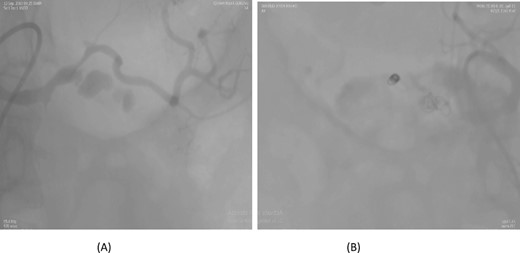

A 57-year-old female underwent a distal pancreatectomy for a pancreatic neuroendocrine tumo. On the 13th postoperative day, the patient presented in a state of shock and intraperitoneal bleeding. A contrast-enhanced CT angiogram revealed the presence of a pseudoaneurysm originating from the splenic artery. The patient underwent endovascular coil embolization of the splenic artery and bleeding stopped and was discharged 3 days following the procedure (Fig. 1).

Case 1. (A) Angiogram pseudoaneurysm from splenic artery. (B) Angioembolization of splenic artery with coil